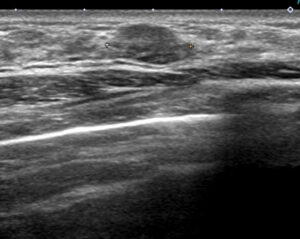

私であれば、エコーで第1印象として「線維腺腫かな?」と思っても(私cat.3)、CELEROにて癌という症例

扁平だけど(私cat.2のように)完全に境界が「クリっ」としていない。

私はこれを境界が「ぼそぼそ」と表現します。

こんな線維腺腫も実際にはありますが、でもやはり(私cat.2とは異なり)

この症例のように乳癌ということがあるのです。

それを経験している私は例えば

こんな(上の症例に比べれば)ぼそぼそ感もほぼなく

私cat2に近い(それでも私は3とします)ものもCELEROしました。